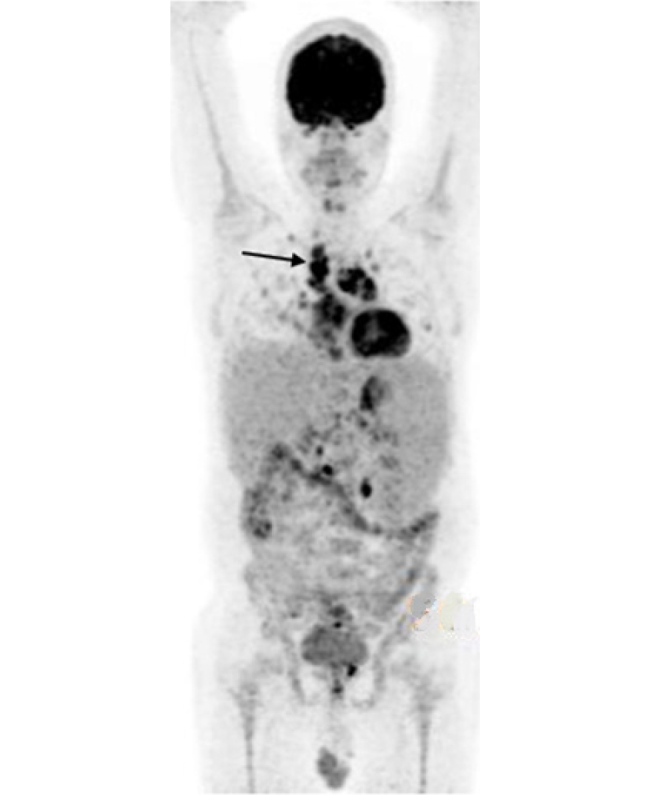

Case description: We present the case of an adult patient with common variable immunodeficiency and interstitial lung disease. He did not receive rituximab due to an adverse reaction and underwent treatment with azathioprine, achieving prolonged remission after treatment discontinuation.